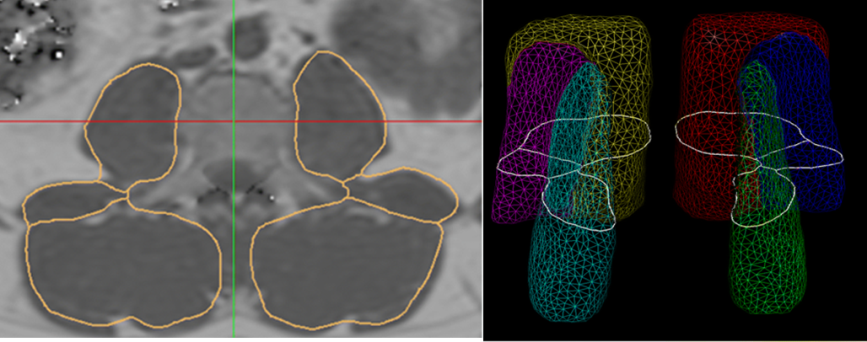

Proton-density fat fraction of the paraspinal muscles has become an important surrogate biomarker in patients with intervertebral disc disease, osteoporosis, sarcopenia, and neuromuscular disorders. The authors developed an automatic segmentation algorithm of the lumbar paraspinal muscles based on water-fat sequences.

Article: Automated assessment of paraspinal muscle fat composition based on the segmentation of chemical shift encoding-based water/fat-separated images